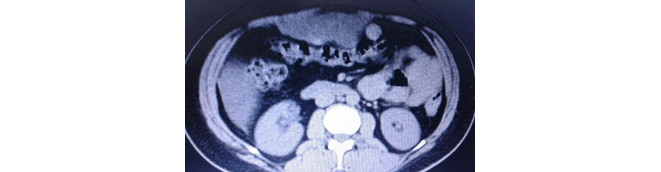

Volver a los detalles del artículo Mesotelioma multiquístico benigno.